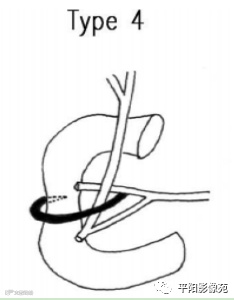

日本学者吉冈根据环状部胰管的走行及汇入情况,将环状胰腺分为四类。

环状部胰管开口于副胰管